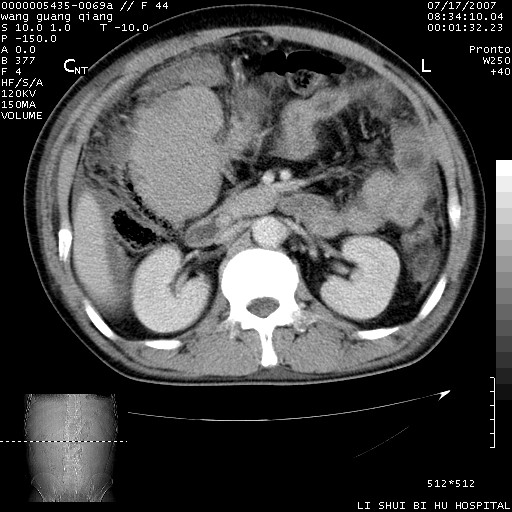

以下是引用dyqct在2007-7-18 10:46:00的发言:[br]胆囊明显增大,壁增厚,明显强化;后下方见大片高密度区,ct值68hu,无强化,周围见多数条纹状高密度影,边界不清。双膈下间隙、肝肾隐窝见带状及片状低密度区。[br]右侧胸壁后缘亦见新月形水样密度区。[br]考虑:1、急性胆囊炎伴周围出血;[br] 2、少量腹水、右侧少量胸腔积液。[br][br][本贴已被 dyqct 于 2007-7-18 10:48:47 修改过]